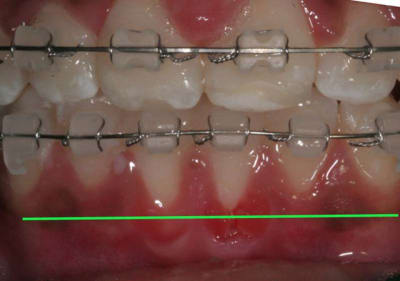

On peut observer un décalage des points inter-incisifs et des rotations des Inc. Inf.

Voir Photo

4 vrokeb - Eugenol